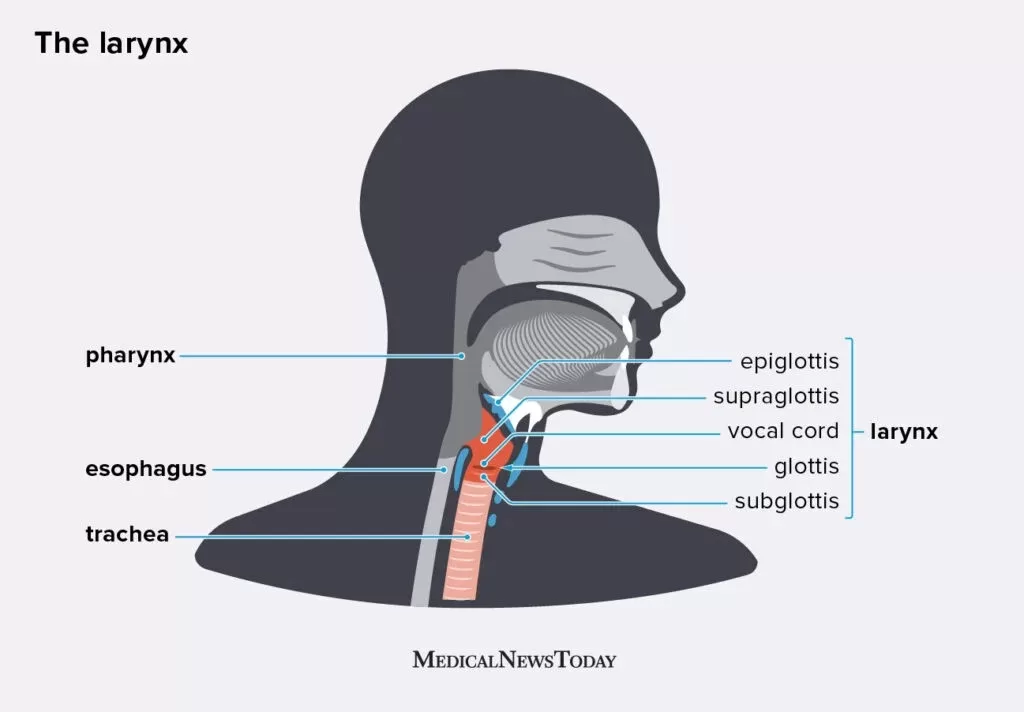

3. Laring

Di dalam laring terdapat sebuah katup yang disebut epiglotis. Epiglotis berfungsi mengatur jalannya makanan dan udara pernapasan sesuai dengan salurannya masing-masing. Di samping itu, pada pangkal tenggorokan terpadat pita suara yang merupakan organ penghasil suara pada manusia. walaupun demikian, saraf kita akan mengatur agar peristiwa menelan, bernapas, dan berbicara tidak terjadi bersamaan sehingga mengakibatkan gangguan kesehatan.